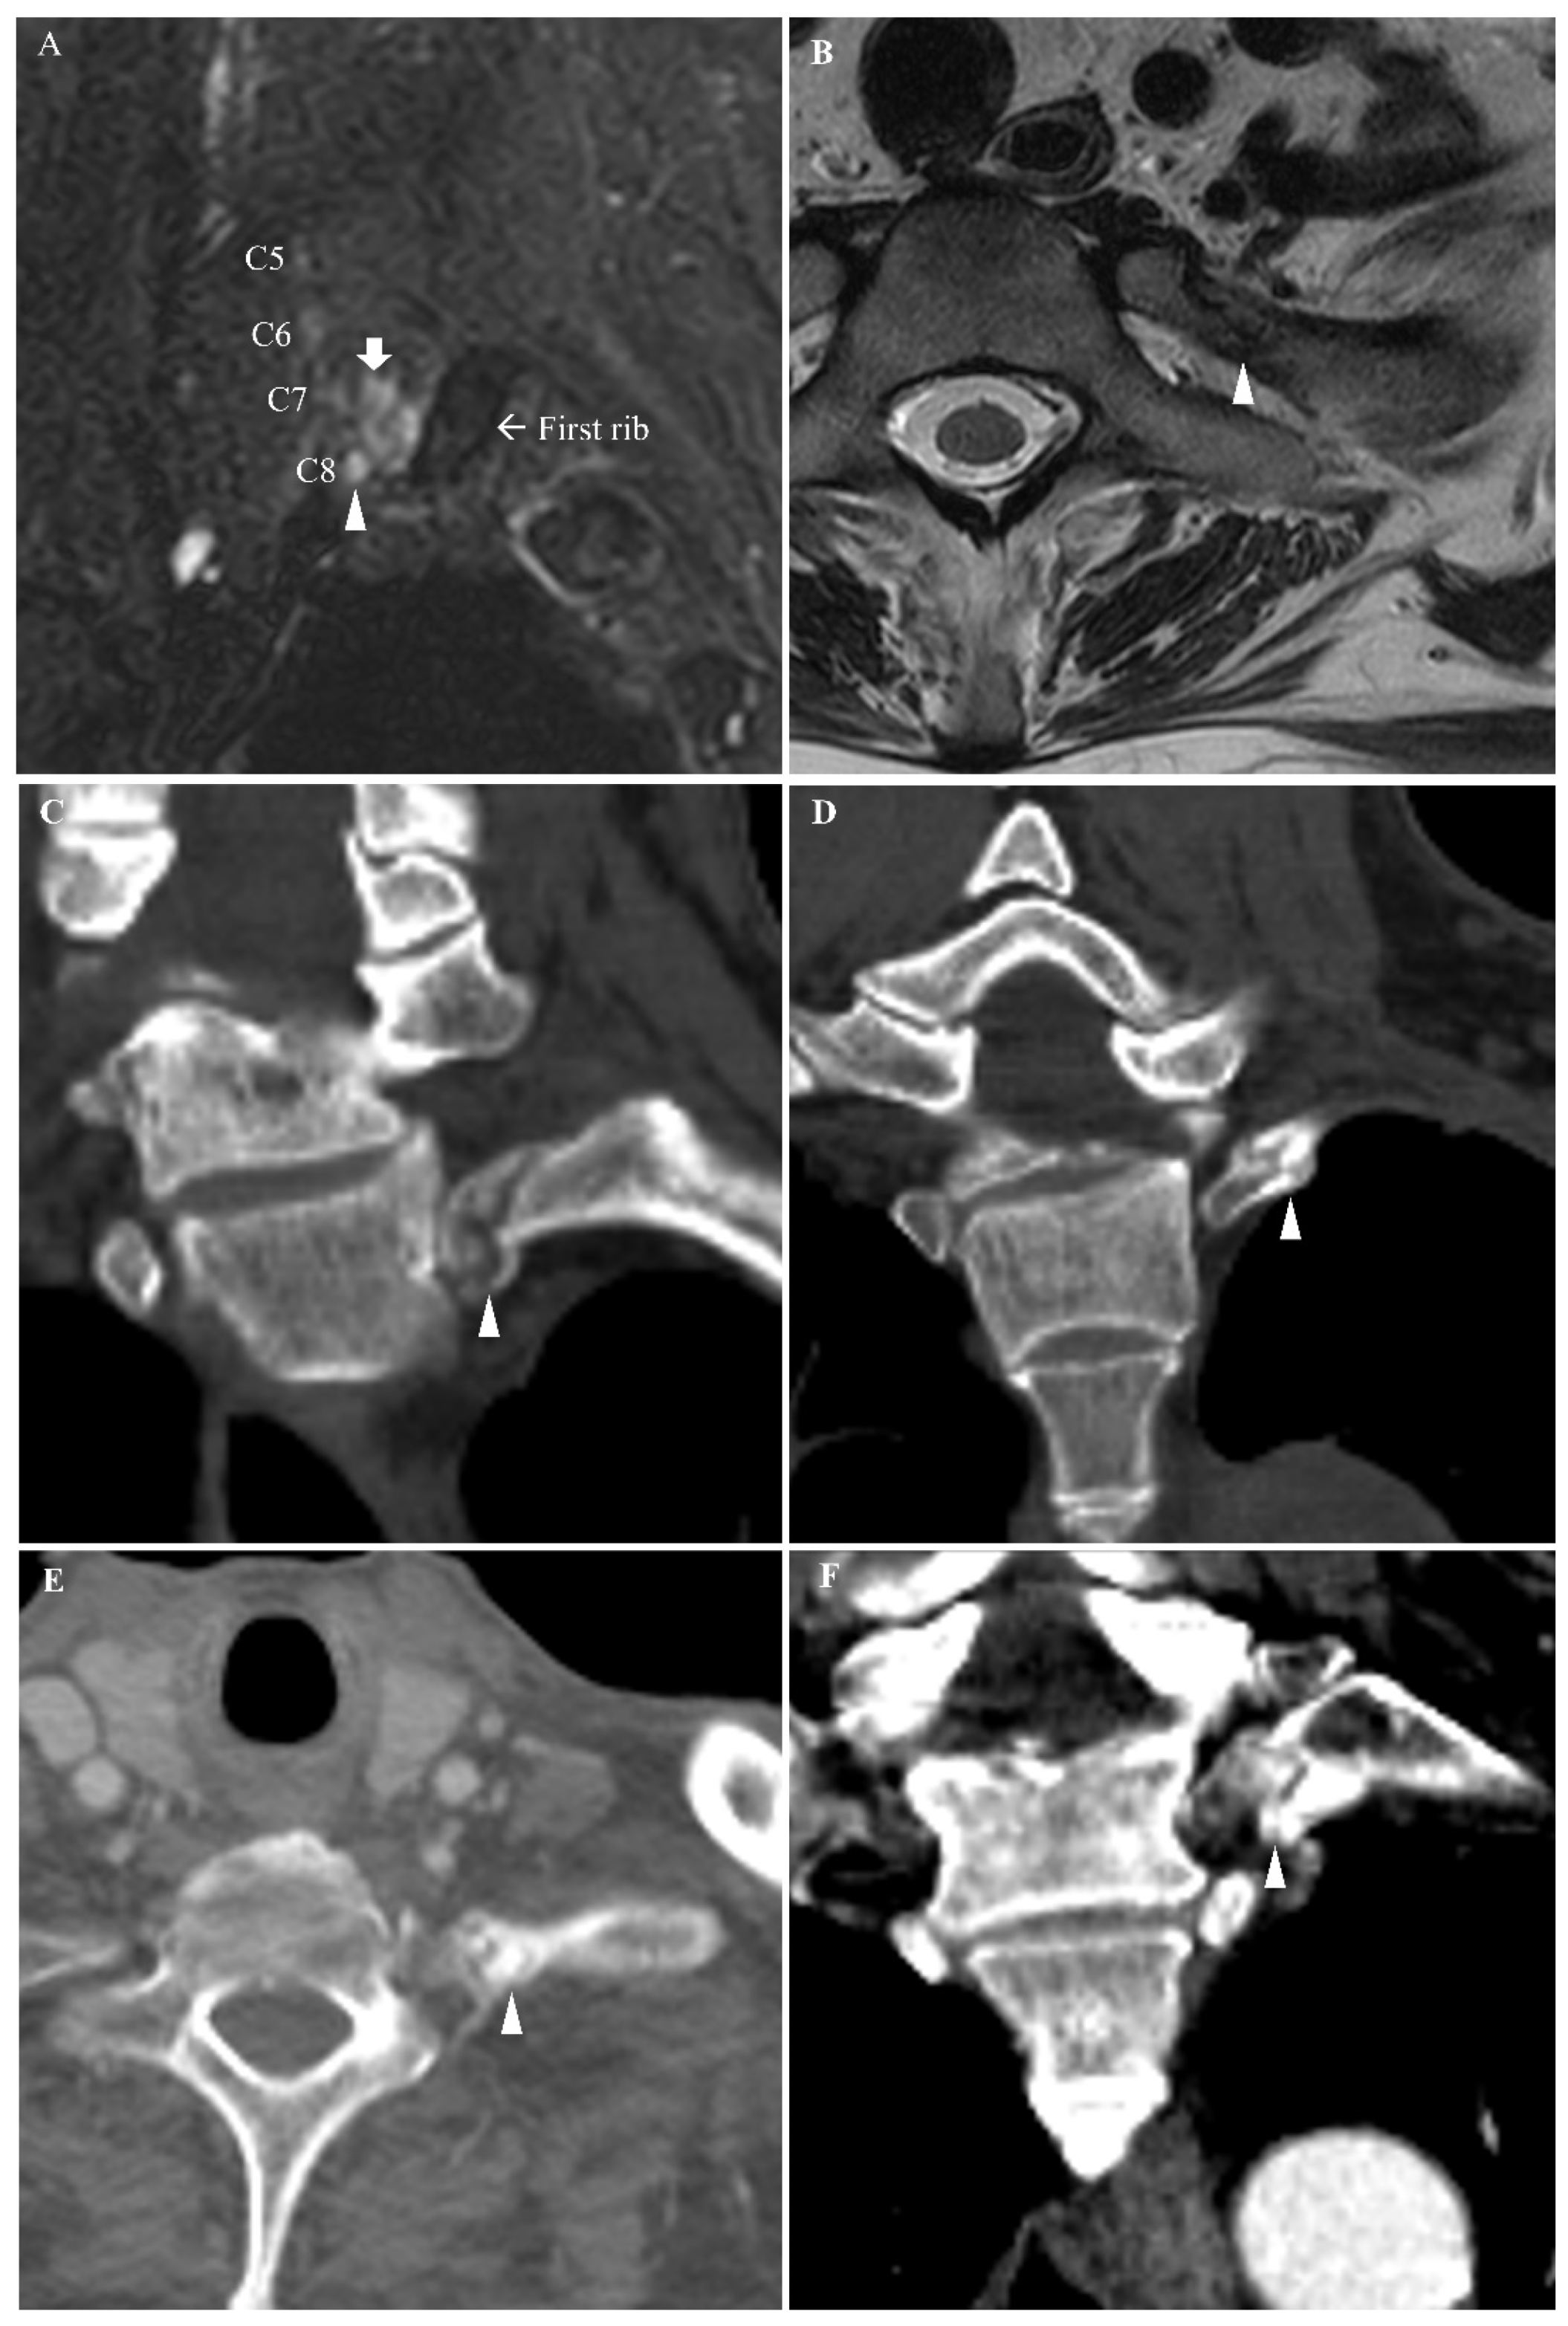

2.1. Case 1

2.2. Case 2

2.3. Case 3